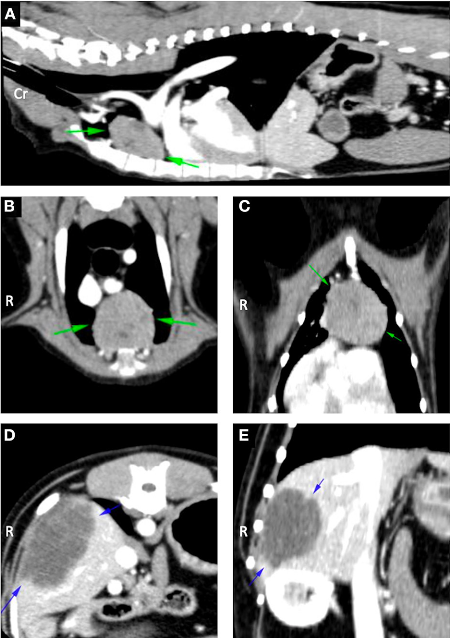

Investigations revealed myasthenia gravis, a severe immune mediate disease that interferes with neurotransmission necessary for muscle contraction and strength. Trevor was also found to have a cranial mediastinal mass which is concurrently reported in approximately 3.4-11% of dogs with this condition, as well as a hepatic mass.

Trevor’s weakness was addressed in the first instance by the neurology team with pyridostigmine bromide, an anticholinesterase medication that improves neurotransmission thereby alleviating the muscle weakness and fatigability. Once his condition had stabilised, the soft tissue surgery team was successfully able to surgically resect both masses.